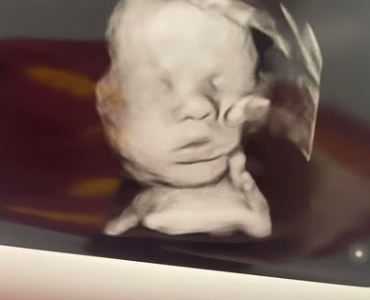

Mutter sieht „Hand Gottes“, die Kopf ihres Babys im Ultraschall hält

Symbolfoto: Shutterstock In dem, was als modernes Wunder bezeichnet wird, sagt eine Mutter aus dem US-Bundesstaat Kentucky, ihr ungeborenes Baby sei von der „Hand Gottes“ berührt worden – und sie hat den Ultraschall, um es zu beweisen. Im April 2022…